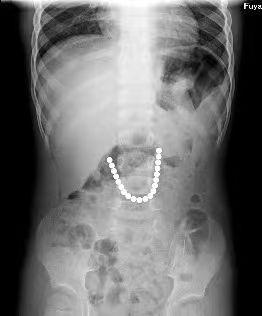

3岁半的男娃吞下20颗磁力珠

磁力珠在体内吸附

形成了一串别致的“圆形项链”

情况紧急,市医院儿科赶紧安排小轩做了X光片检查,发现小轩的肠道内整齐排列着20颗磁力珠。

胃镜探查结果显示,20颗磁力珠形成圆环状,停留在小轩的十二指肠降部。幸运的是,磁力珠没有继续掉落,且胃镜探查到的磁力珠数量和X光片显示数量一致。